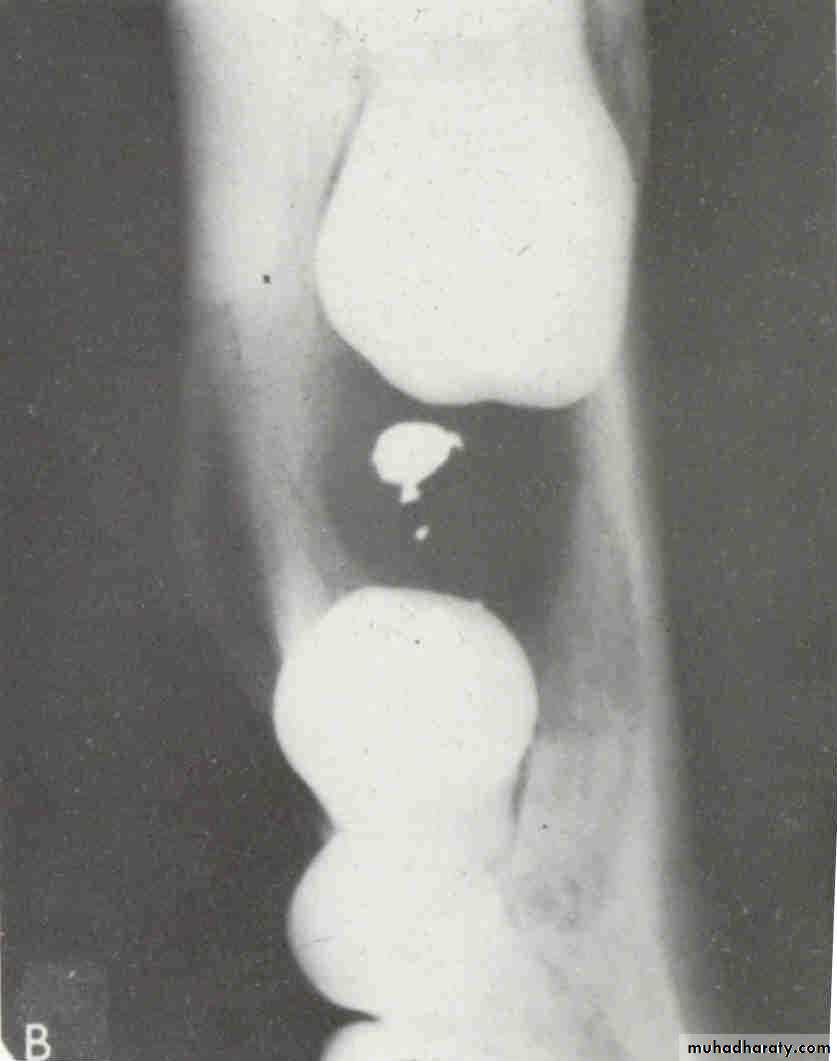

• A lesion (developmental salivary gland

• defect) below the IAC• (non- odontogenic origin).